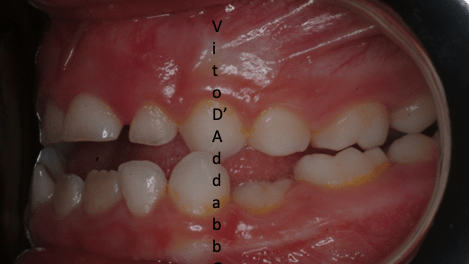

dopo – fase 2

dopo – fase 1